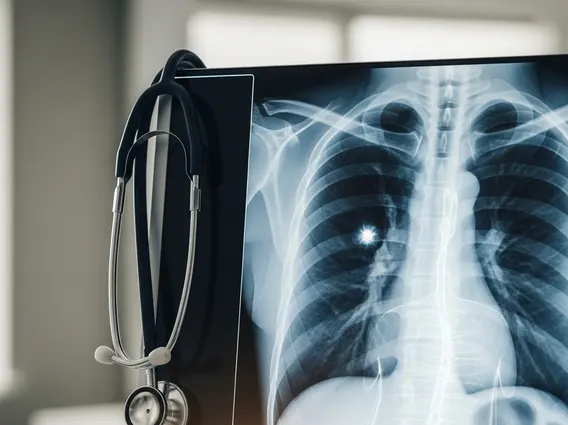

Um Anzeichen Lungenkrebs frühzeitig zu erkennen, ist es wichtig, nicht nur auf einzelne Symptome zu achten, sondern auch auf deren Kombination und Persistenz. Ein Arzt kann durch eine gründliche Anamnese, körperliche Untersuchung und gegebenenfalls weitere diagnostische Maßnahmen wie Röntgenbilder des Brustkorbs, Computertomographie (CT) oder eine Bronchoskopie eine genaue Diagnose stellen. Zögern Sie nicht, Ihre Bedenken offen anzusprechen, denn nur so kann eine zeitnahe Abklärung erfolgen. Laut der Deutschen Krebshilfe kann eine frühzeitige Diagnose die 5-Jahres-Überlebensrate bei Lungenkrebs signifikant verbessern.

Die Diagnose von Lungenkrebs beginnt in der Regel mit einer ausführlichen Anamnese und körperlichen Untersuchung durch den Arzt. Bei Verdacht folgen bildgebende Verfahren wie Röntgenaufnahmen des Brustkorbs und eine Computertomographie (CT). Bestätigt wird die Diagnose durch eine Biopsie, bei der Gewebe aus der Lunge entnommen und mikroskopisch untersucht wird. Dies kann mittels Bronchoskopie, Nadelbiopsie oder in manchen Fällen auch chirurgisch erfolgen. Zusätzliche Untersuchungen wie PET-CT oder MRT dienen der Stadieneinteilung und Planung der Therapie.